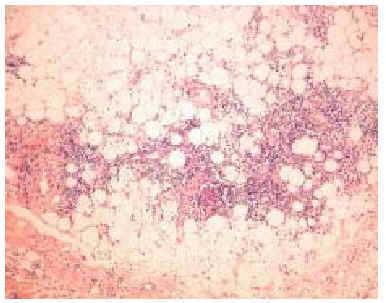

En septiembre de 1999 presentó un nuevo brote de lesiones cutáneas clásicas de dermatomiositis, así como 5 lesiones nodulares en ambos miembros superiores, de unos 3 cm de diámetro, dolorosas, induradas, de superficie poiquilodérmica, sin sintomatología muscular ni elevación de las enzimas musculares. Se realizó una biopsia cutánea de un nódulo del brazo que puso de manifiesto una degeneración vacuolar focal de la capa basal epidérmica y un leve infiltrado inflamatorio linfohistiocitario perivascular en la dermis. Lo más llamativo fue la presencia de una paniculitis de predominio lobulillar con linfocitos, histiocitos y células plasmáticas (fig. 2). En algunas zonas los linfocitos formaban acumulaciones donde se insinuaba un centro germinal (fig. 3) y en otras infiltraban la pared de los vasos (fig. 4).

Fig. 2.--Paniculitis lobulillar con linfocitos y células plasmáticas. (Hematoxilina-eosina, x40.)